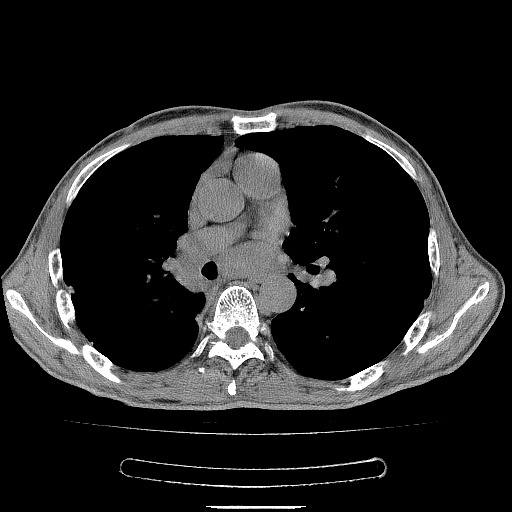

男性患者,63岁。右侧胸背部疼痛2月,加重一周。

考虑:右肺中央型肺癌并右肺下叶不张;两肺尖继发性肺结核。

还有纵隔多处肿大淋巴结及肋骨的改变、两肺多发结节灶。

考虑右中心型肺癌并右下肺不张,肺及纵隔,左肋骨转移。

右肺下叶支气管狭窄闭塞,右下肺不张,气管前间隙淋巴结肿大,两上肺散在分部粟粒灶,沿肺血管支气管束分部,血管支气管束走形较为光滑。考虑右肺中心型肺癌合并肺不张,纵隔淋巴结转移,两上肺癌性淋巴管炎

1)右肺下叶中心性肺癌并纵隔淋巴结转移,两肺转移,左侧肋骨转移。2)双肺上叶继发性结核。

右肺下叶中心性肺癌并纵隔淋巴结及两肺、左侧肋骨转移。双肺上叶继发性结核表现。